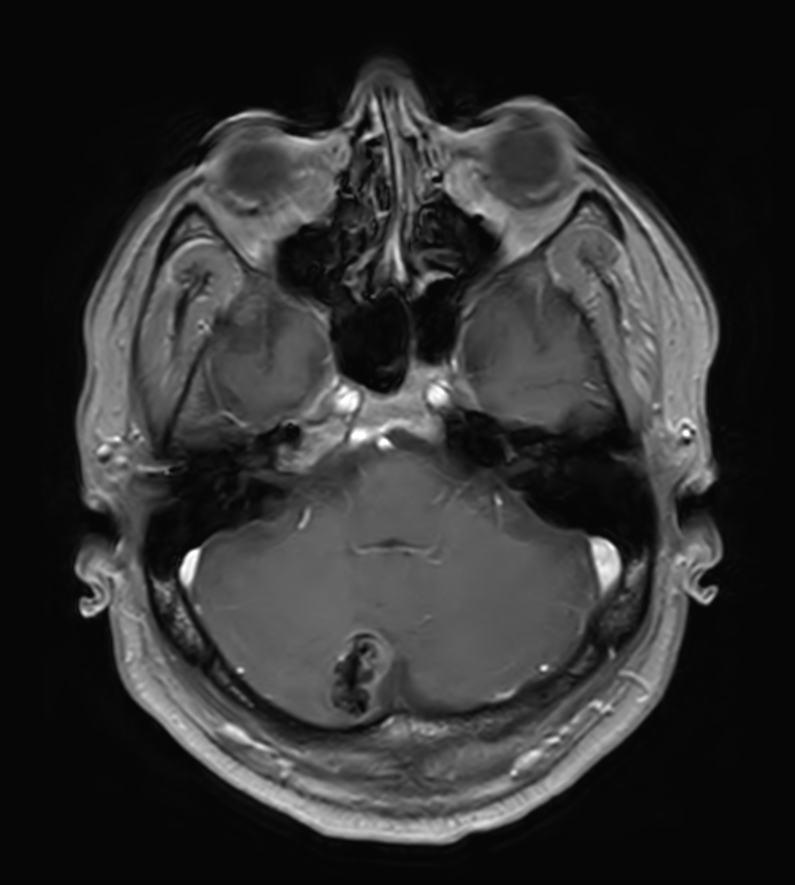

T2w TSE MultiVane XD

Patient with a lesion in the cerebellum. The ExamCard includes Compressed SENSE to accelerate the entire exam and techniques for motion reduced imaging (MultiVane XD), 3D imaging to acquire high resolution data in multiple directions, 3D susceptibility weighted imaging (SWIp), angiography sequences (Time-of-Flight and Contrast-Enhanced MRA with both arterial and venous phases), DTI with MultiBand SENSE to acquire a high number of diffusion directions in a short scan time and EPIC Brain to bring down any residual distortion.